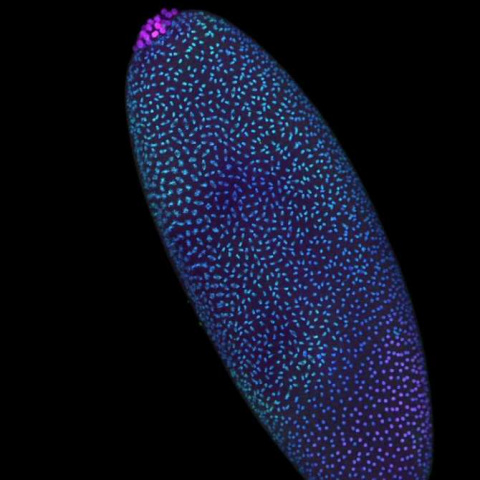

Desentrañando cómo se origina el cáncer infantil más frecuente